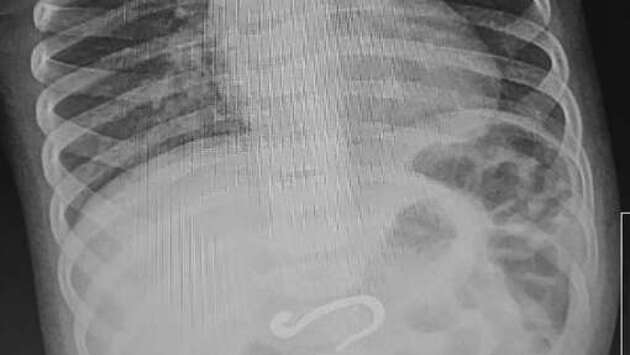

В Челябинске врачи достали из младенца металлический крюк. О необычном клиническом случае рассказали в Челябинской областной детской клинической больнице. Восьмимесячный мальчик поступил на днях в экстренный приемный покой ЧОДКБ с подозрением на проглоченный колпачок от ручки. Однако рентген показал, что в его желудке находится металлический крюк внушительных размеров, который уже частично погрузился в двенадцатиперстную кишку. Сначала врачи решили переместить инородное тело из кишки в более просторное место желудка, а затем подцепить и аккуратно извлечь наружу. Операция длилась час и прошла успешно. Выяснилось, что извлеченный крюк не вызвал внутренних повреждений и маленький пациент отправился домой.